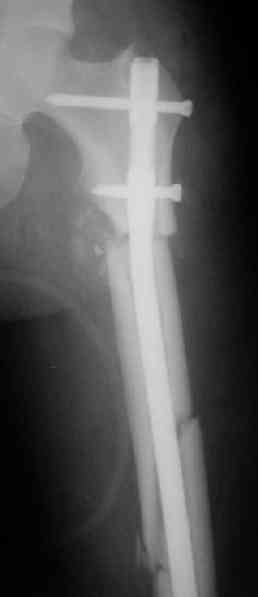

Вот несколько. С тисками и трубой на днях сделаем.

> Вот несколько. С тисками и трубой на днях сделаем.

Саша, последний штифт, пожалуй, перегнули?

> Саша, последний штифт, пожалуй перегнули?

Там заход сделан как для прямого штифта, не через вертел.